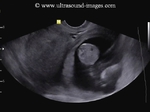

Pregnancy in one horn of uterus with two horns (cornu)

The above ultrasound images show a bicornuate uterus with a gestation sac in the right cornu (1). The empty left cornu (2) shows typical decidual changes of pregnancy. The 3rd image (right) is a sagittal section through each cornu.

Images courtesy of Dr. Ravi Kadasne, UAE.